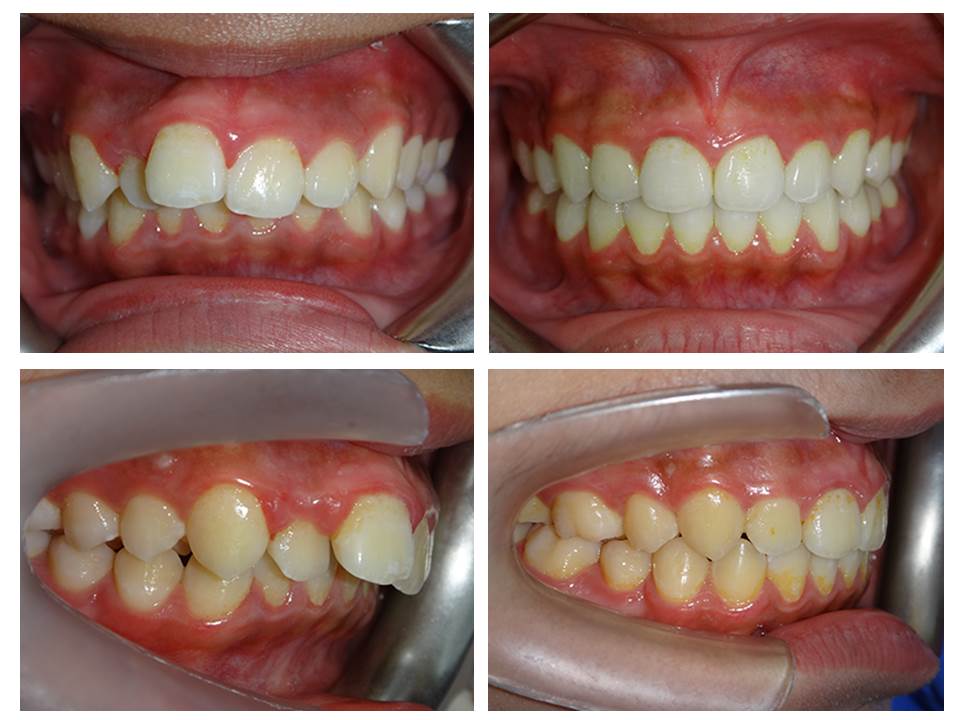

自鎖式矯正器不拔牙矯正

矯正訴求: ■ 咬合不正 ■ 牙齒凌亂